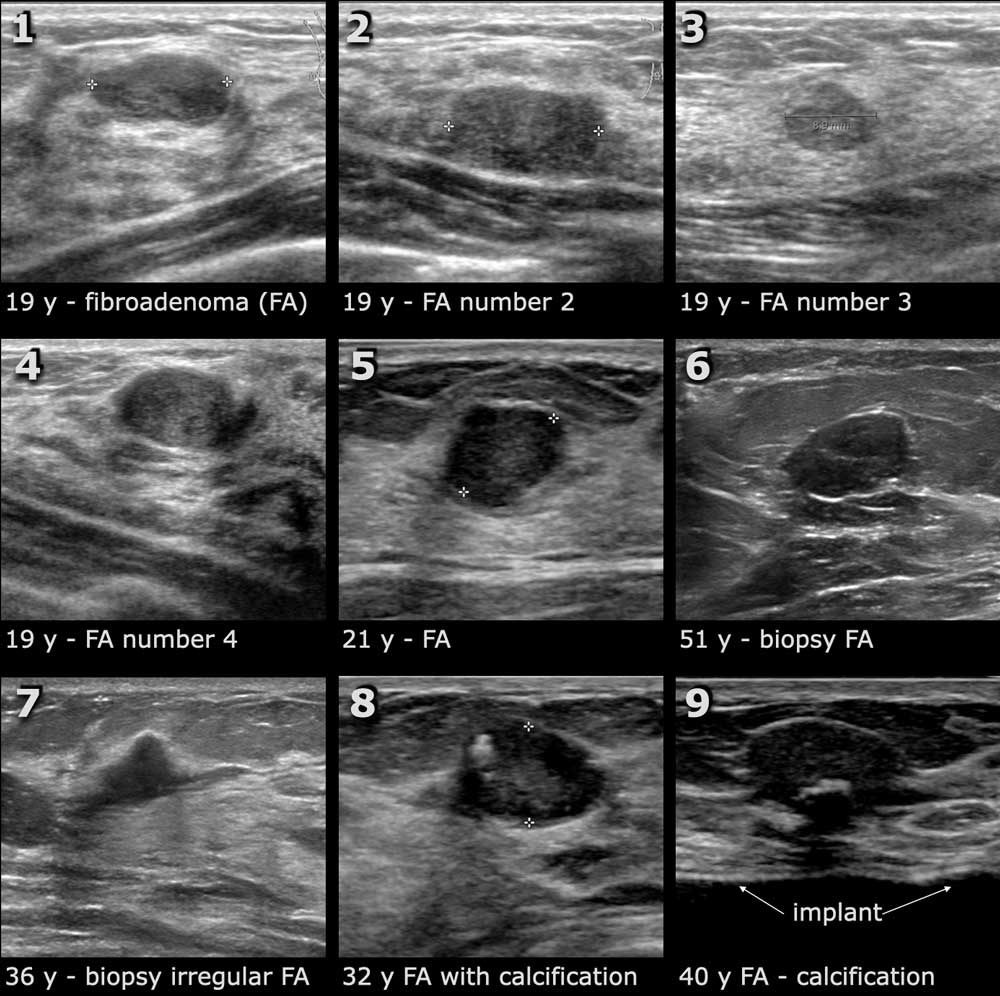

Breast ultrasound is a safe, non-invasive imaging technique that provides detailed insights into breast tissue. It is an ideal solution for women with dense breast tissue, a common trait among Indian women, where mammograms may not always provide clear results. For Asha, the thought of undergoing a procedure that didn't involve radiation and was painless brought a sense of relief.